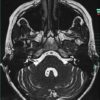

U dây VIII - Ảnh 2

U dây VIII

» Thông tin: Nữ giới – 35 tuổi.

» Lâm sàng: Điếc đột ngột.